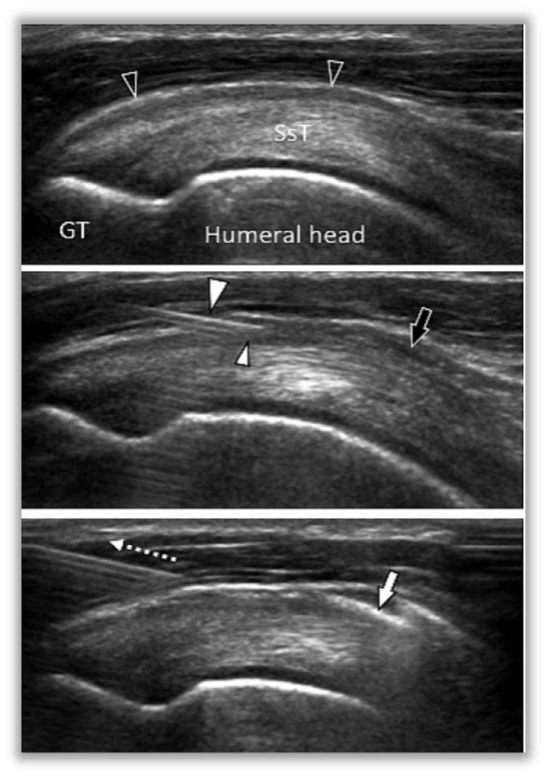

Figure 1 - Schematic of ultrasound-guided subacromial bursa injection for rotator cuff impingement (Molini et al., 2012)

Figure 2 - Visualization of needle during ultrasound-guided subacromial bursa injection for rotator cuff impingement (Molini et al., 2012)